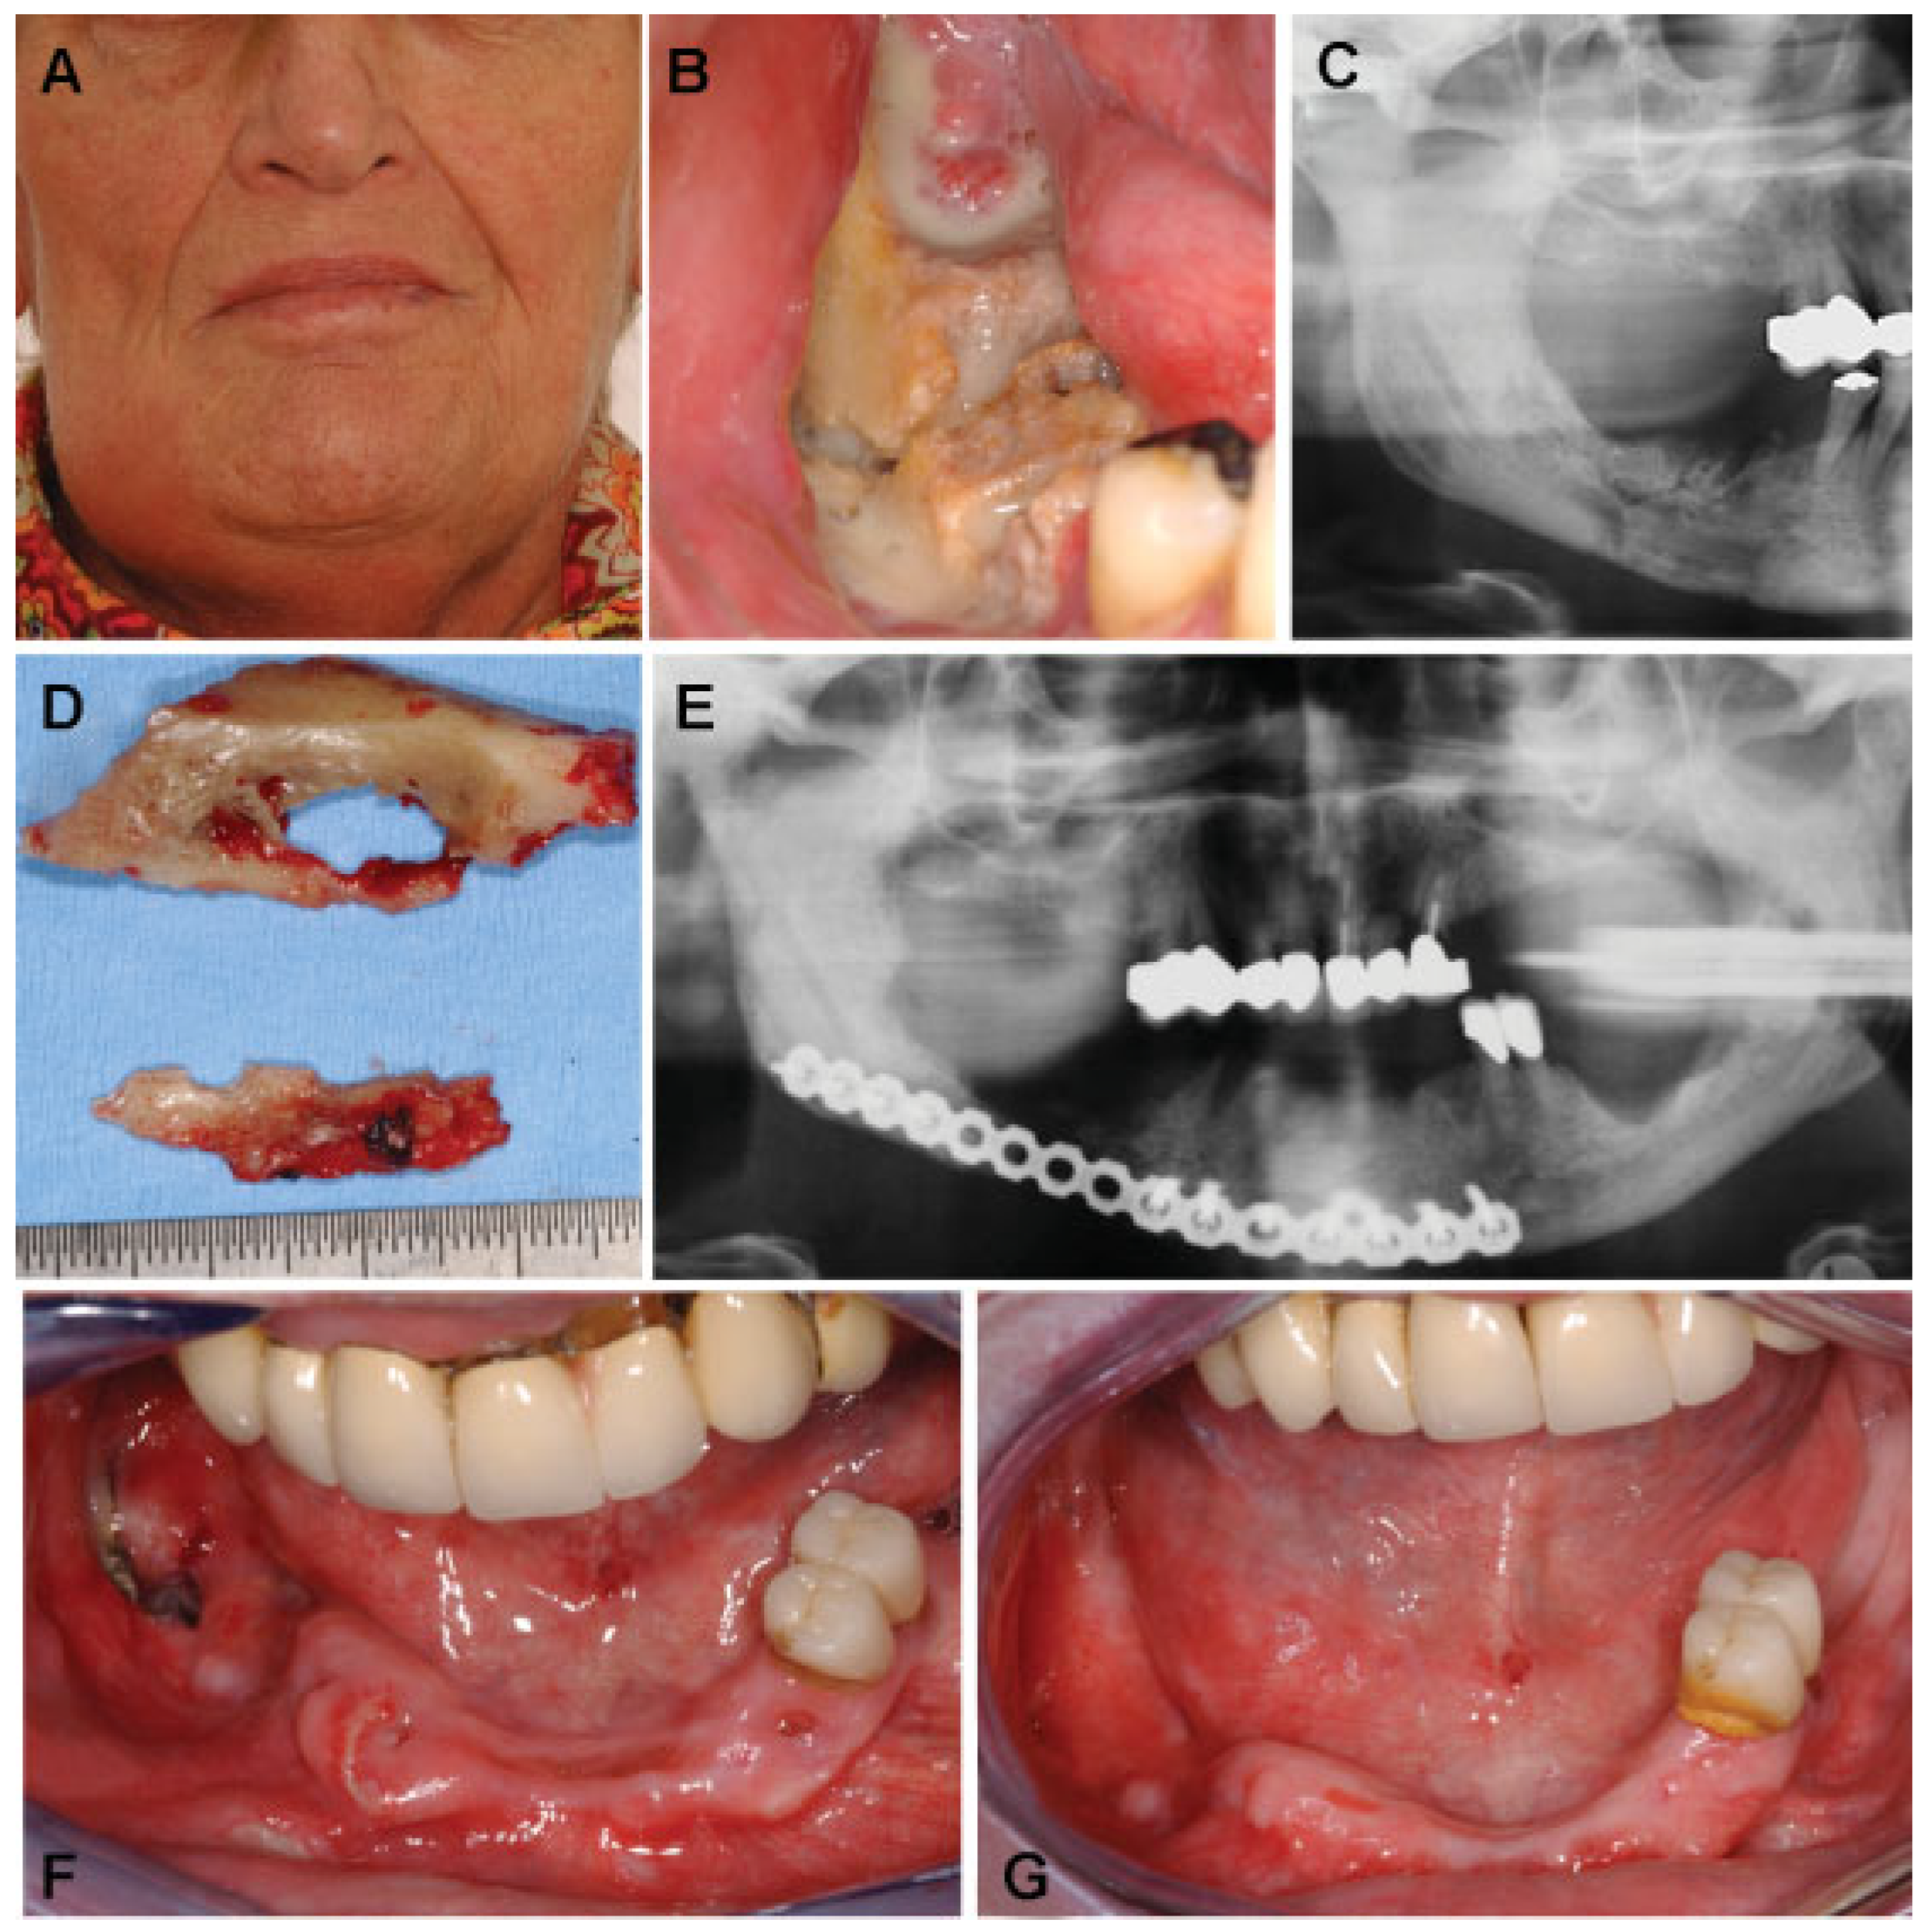

| Patient | Age | Sex | Underlying Disease | Bisphosphonate | Localization of Fracture |

|---|---|---|---|---|---|

| 1 | 65 | F | Breast cancer | Zoledronate (i.v.) | Right mandibular body/angle |

| 2 | 72 | M | Prostate cancer | Zoledronate (i.v.) | Left mandibular body |

| 3 | 91 | M | Prostate cancer | Zoledronate (i.v.) | Left mandibular angle |

| 4 | 73 | F | Multiple myeloma | Zoledronate (i.v.) | Left mandibular body |

| Patient | Treatment | Outcome |

|---|---|---|

| 1 | Sequestrotomy and removal of necrotic bone parts including segmental resection, open reduction and rigid internal fixation (AO Titanium 2.4 unilock) (DePuy Synthes, Germany) | Delayed mucosal healing (initial wound dehiscence with complete mucosal healing after local disinfectant measurements) |

| 2 | Sequestrotomy and removal of necrotic bone parts and application of external fixation | Stable pseudarthrosis and mucosal healing |

| 3 | Sequestrotomy and removal of necrotic bone parts, open reduction and rigid internal fixation (AO titanium 2.4 unilock) | Delayed but complete mucosal healing |

| 4 | Sequestrotomy and removal of necrotic bone parts, open reduction and rigid internal fixation (Matrix mandible preformed plate) (DePuy Synthes, Germany) | Delayed mucosal healing with a small area of intraoral bone exposure (no plate exposure, no extraoral fistula) |